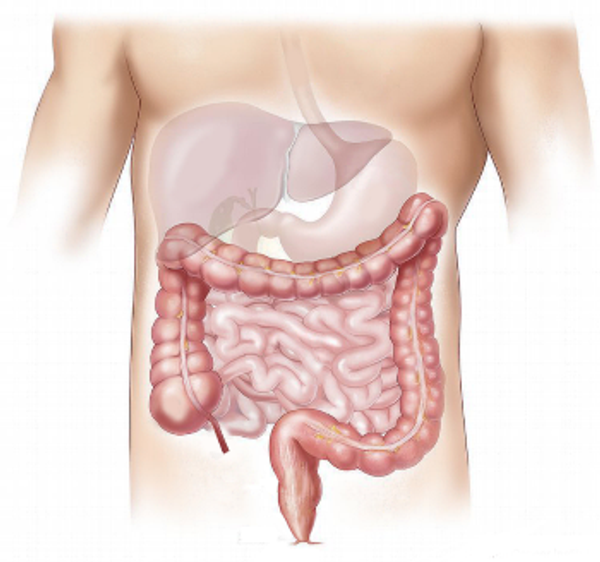

Verdauung, und das Wort sagt schon alles, bedeutet buchstäblich die Aufspaltung von Nahrung. Jeder weiß, dass man Essen und Trinken zu sich nehmen muss, um zu leben, dass man dies im Wesentlichen durch den Mund tut und dass das, was man nicht verwerten kann, den Körper wieder durch den Darm verlässt. Dieser Prozess "vom Mund zum Darm" wird als Verdauung bezeichnet und dauert im Durchschnitt zwischen 24 und 48 Stunden.

Die Nahrung gelangt also durch den Mund in den Körper, wo sie zerkaut und mit Speichel vermischt wird, damit sie leicht und mit Hilfe der Zunge geschluckt werden kann. Anschließend wird sie langsam und geordnet durch die Speiseröhre in den Magen befördert, wo sie mit Magensaft vermischt wird. Dieser Magensaft, der sehr säurehaltig ist, bewirkt, dass die Nahrung in kleine Stücke zerfällt. Dies dauert im Durchschnitt etwa drei Stunden. Über den 12-Finger-Darm gelangt sie dann in den Dünndarm, wo sie in noch kleinere Teilchen zerlegt wird. Bei diesen Partikeln handelt es sich um Glukose, Aminosäuren, Fettsäuren, Vitamine und Mineralien, die in den Blutkreislauf aufgenommen werden können, sowie um Ballaststoffe und Abfallprodukte, die den Körper schließlich über den Dick- und Enddarm in Form von Stuhlgang verlassen.

Im Allgemeinen erreichen kleine Nährstoffe über den Dünndarm und den Blutkreislauf zuerst die Leber. Die Leber kann man eigentlich am besten mit einer Art Sieb vergleichen. Sie kontrolliert ständig die Nährstoffe, indem sie das Blut filtert, das über die Pfortader durch die Leber fließt (etwa eineinhalb Liter pro Minute). Alle guten und nützlichen Stoffe werden dann durchgelassen und die schlechten, zum Beispiel Giftstoffe wie Alkohol, werden aufgehalten und abgebaut, damit sie den Körper unter anderem über den Urin wieder verlassen können.

Neben der Leber sind auch die Gallenblase und die Bauchspeicheldrüse am Stoffwechsel beteiligt. Die Gallenblase, ein Beutel, in dem die Galle gespeichert wird, wird aktiv, wenn Fette abgebaut werden müssen. Die Bauchspeicheldrüse liefert Säfte, mit denen sowohl Kohlenhydrate als auch Fette und Eiweiße verkleinert werden können. Die Bauchspeicheldrüse ist auch für die Produktion der Hormone Insulin und Glukagon zuständig, die den Blutspiegel regulieren.